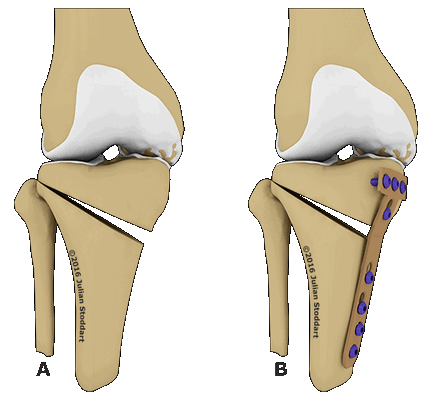

Схематичное изображение проведения операции.

Корригирующая остеотомия коленного сустава — операция, устраняющая врожденные и приобретенные костные деформации. Во время хирургического вмешательства врач иссекает заранее обозначенный участок костной ткани и соединяет свободные фрагменты костей имплантатами. В результате ось механической нагрузки переносится на здоровый участок сустава. Операция проводится под полной или спинальной анестезией. После лечения ортопед фиксирует нижнюю конечность пациента гипсовой повязкой на время восстановления. Проводится реабилитация.

Остеотомия с металлоконструкцией.